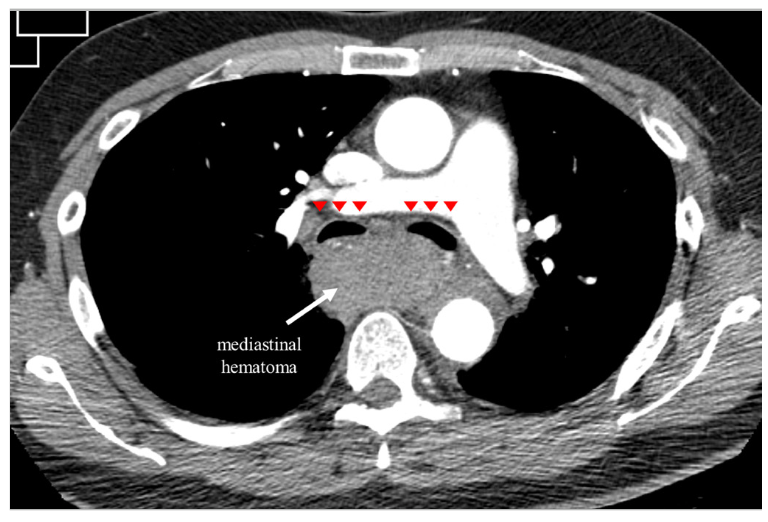

A 65-year-old man who presented with lateral ST-segment-elevation myocardial infarction was referred for primary percutaneous coronary intervention. J-wire and 5.2-Fr JR4 diagnostic catheter progression through right radial artery access was hampered by radial artery spasm and subclavian artery tortuosity. Then, a hydrophilic-coated guidewire was used to assist catheter advancement into the aortic root. Coronary angiography revealed an acute occlusion of the first obtuse marginal artery, which was successfully revascularized with 2 consecutive drug-eluting stents (Video Series). Three hours later, the patient developed symptoms of pleuritic chest pain, dyspnea, stridor, and evolved with shock. Thoracic computed tomography (CT) angiography revealed a large mediastinal hematoma compressing the airway (Figures 1C, 1E and Figure 2). Due to high index of suspicion and after multidisciplinary heart team discussion, an upper limb angiography was performed, which detected perforation of a small collateral branch of the brachiocephalic artery (Figure 1A). The perforation was treated with a single coil embolization, resolving the active bleeding (Figure 1B and Figure 3). Control CT imaging at 2-month follow-up revealed complete resolution of the mediastinal hematoma and airway compression (Figures 1D, 1F).